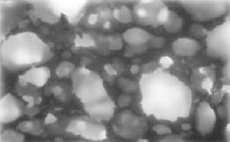

Unique Interconnected Porosity

Provides vital environment for osteointegration and enhanced osteocyte formation.1-3,5

MICROSPACES (1-10 M):

Stimulate cell attachment and growth.1

MIDIPORES (1O-100 M):

Support osteocyte accommodation and proliferation.1

MACROPORES (> 100 M):

Facilitate penetration of osteogenic cells and vascular structures.1